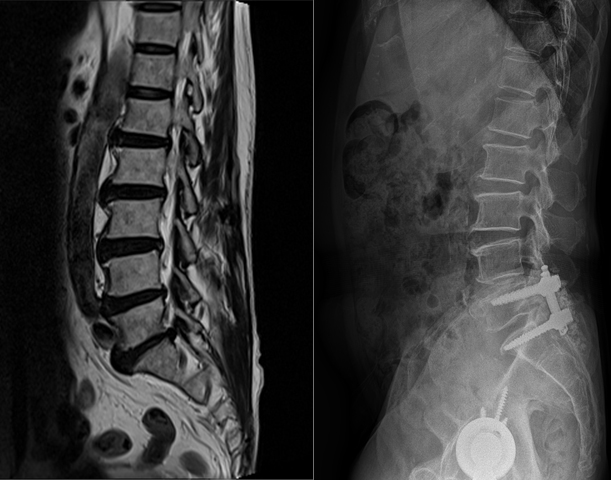

척추 불균형이 심하지 않고, 증상이 심하지 않을 경우에 보존적 치료를 시행하며, 약물 치료 및 물리 치료, 운동 치료 신경 차단술 등이 있습니다. 보존적 치료에도 반응을 하지 않는 경우로 심한 요통을 호소하는 경우, 척추 불안정성으로 임상 증상을 보이는 경우, 요통과 하지 방사통 혹은 마비증상을 보이는 경우 수술의 대상이 될 수 있는데, 수술적 치료로는 단순 신경 감압술, 후방경유 척추체간 융합술, 전-후방 경유 유합술 등이 있으며 측방 전위, 관상면 변형, 시상면 변형의 정도에 따라 수술적 치료의 정도를 결정합니다.

척추 뼈 사이의 움직임을 유지하면서 어긋나지 않도록 지지해 주기 위해 인대라는 것이 존재하는데, 목 부위 경추에서 꼬리뼈 근처의 천추까지 척추 전체를 위에서부터 아래까지 정렬을 유지하기 위해서도 인대가 존재합니다. 이러한 인대에는 여러 종류가 있는데, 척추의 정렬 및 안정화, 그리고 운동성을 유지하기 위해 존재하는 종인대 중 척추의 전방에서 지지하는 것이 전종인대이며, 척추체의 뒤쪽에서 지지하는 것이 후종 인대입니다. 이 후종 인대가 뼈처럼 단단하게 굳어지며 두꺼워지는 변화를 일으켜 척추관을 지나는 신경을 압박함으로써 신경장애 (척추신경근증 혹은 척수증)가 나타나는 질환을 후종 인대 골화증이라고 합니다.

이 질환의 원인은 불명확하지 않으나 주로 한국, 일본 등의 동양인에게서 상대적으로 자주 나타나고, 경추 후종 인대 골화증 환자의 부모나 형제에서의 발병률이 일반인보다 높은 것으로 보아 유전적, 인종적인 요소가 많이 작용하는 것으로 알려져 있습니다. 실제로 몇몇 유전자가 후종 인대 골화증에 연관되어 있다는 보고가 있습니다. 외상, 당뇨병, 비만, 면역 질환, 강직성 척추염, 미만성 골과다증 등과도 관련이 있다고 보고되고 있으며, 발생 부위는 주로 목 부분인 경추에서 발생하지만 흉추나 요추에서도 드물게 발생합니다.

많은 경추 후종 인대 골화증 환자는 무증상 또는 초기에 경부(목 부위) 통증과 위화감, 압박감의 증세만을 호소합니다. 그러다 진행이 되면 후종인대가 딱딱해지고 점차 커지면서 신경을 압박하여 팔이나 손의 저림, 통증, 감각 저하, 근력 저하로 시작하여 점차 다리의 근력 저하 및 감각 이상, 보행장애, 배뇨나 배변장애가 나타나며, 외상으로 인해 더 악화되거나 더 심한 경우에는 팔다리의 마비도 올 수 있습니다. 경추 후종 인대 골화증의 증상은 주로 신경근 압박에 의한 방사통 보다는 척수 압박에 의한 척수병증을 보이는 경우가 대부분입니다. 80-95%의 환자에서 증상은 천천히 진행되나 경미한 외상 또는 경추의 과도한 신전에 의해서 증상이 급격하게 악화되어 사지마비가 올 수도 있습니다.

단순 방사선 검사

후종인대 골화증의 경우 골변성을 동반하기 때문에 단순 방사선 검사상에서 발견이 가능한 경우도 있습니다. 하지만 정밀한 진단을 위해서는 전산화 단층촬영(CT), 자기공명촬영(MRI)가 반드시 필요합니다.

전산화 단층 촬영

후종인대 골화증 검사에서 가장 중요한 검사입니다. 전산화 단층촬영은 골화된 종괴의 모양과 크기, 척추관 협착과 척수 압박 정도를 정확히 알 수 있습니다.